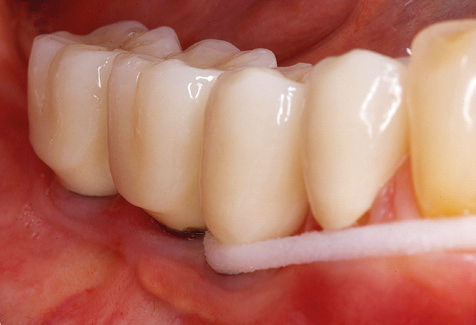

Standardised and regular risk-adapted care in the scope of SPT is the key to treatment success for the clinical long-term success in periodontically compromised patients. This is particularly true for patients fitted with implants following successfully completed periodontal treatment (Fig. 11a and b).